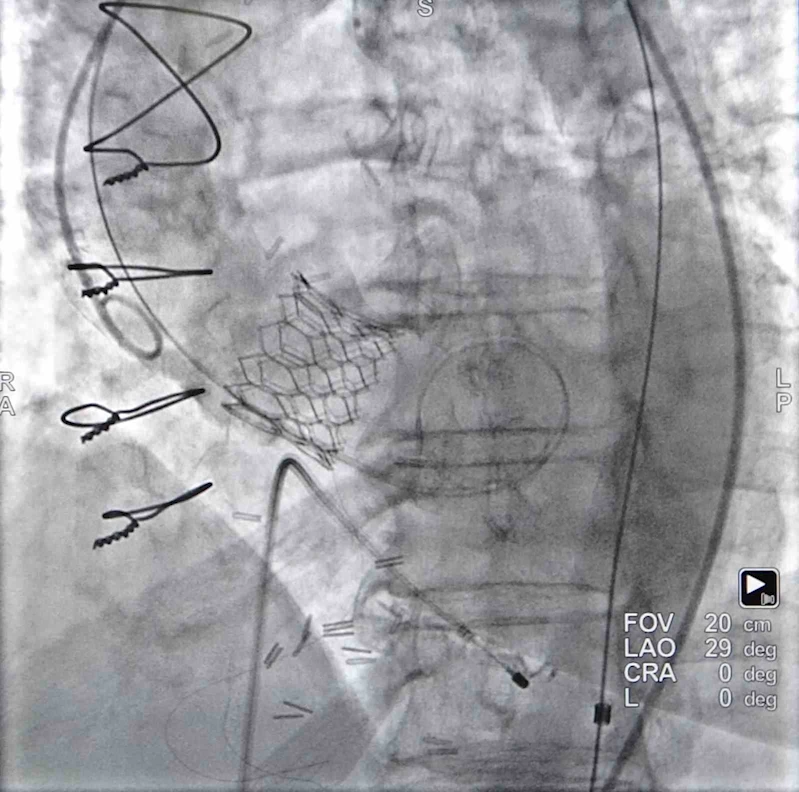

Gürcü Nunu Tsutsunava yaklaşık 10 ay önce memleketinde koroner bypass ameliyatı oldu. Ameliyatın ardından yaraları iyileşmeyen, nefes darlığı ve erken yorulma gibi şikayetleri devam eden Tsussunava, sağlığına tekrar kavuşmak için Trabzon'da Medical Park Karadeniz Hastanesi'ne başvurdu. Kalp ve Damar Cerrahisi'nden Dr. Öğretim Üyesi Tuncay Erden'e muayene olan Gürcü hasta için bir heyet oluşturuldu. Aort kapağında ileri derecede daralma olduğu tespit edilen Gürcü kadın için kapalı yöntemle aort kapağı değiştirme yapılmasına karar verildi. Kardiyoloji Uzmanı Doç. Dr. Zeydin Acar'ın da katıldığı operasyonda yaklaşık 1 saatlik bir sürede yapılan işlem ile Gürcü kadının aort kapağı değiştirildi. Trabzon'da tekrar sağlığına kavuşan Nunu Tsutsunava, hayata yeniden Trabzon'da "Merhaba" dedi.

Gürcistan'dan gelen hasta için yapılan operasyonu anlatan Kardiyoloji Uzmanı Doç. Dr. Zeydin Acar, yaklaşık 10 ay önce bypass ameliyatını olan hastanın tekrar göğsünü açarak ameliyat etmenin zor olduğunu belirterek, "Bu hastamız nefes darlığıyla kalp damar cerrahi arkadaşımıza başvurmuş. Daha önce de bu hasta bypass olduğu için bypassla alakalı birtakım şikayetlerden dolayı doktor Tuncay Erden hocamıza başvurmuş. Tabii yaptığımız tekniklerle nefes darlığı devam edince buna aort kapak darlığı tanısı koyduk. Daha önce baypas olduğu için tekrardan göğsü açmak zor oluyor bu hastalarda. Komplike oluyor. Hem yaşlı hastalar hem diğer durumlardan dolayı o yüzden bu hastamıza biz tekrar ameliyat etmeden kapak yerleştirmeyi kalp takımı olarak uygun gördük. Hastamızı yaptırdık gerekli tetkiklerini yaptık. Kapak içinde uygun olunca yaklaşık bir saatlik bir operasyonla aort kapağını değiştik. Bugün üçüncü günümüz inşallah taburcu edeceğiz" diye konuştu.

Tsutsunava'nın hastaneye başvurduğunda nefes darlığı ve erken yorulma gibi şikayetlerinin olduğunu belirten Kalp ve Damar Cerrahisi'nden Dr. Öğretim Üyesi Tuncay Erden, "Hastamız yaklaşık 10 ay önce Gürcistan'da koroner bypass ameliyatı olmuştu. Sonrasında yaralarında sıkıntı olduğundan dolayı bu yaraların tedavisi amacıyla bize müracaat etmişti. Nefes darlığı, erken yorulma şikayetleri de vardı. Kalbine eko çektirdik. Bu ekoda aort dediğimiz kapakta ileri derecede daralma olduğu saptandı. Ani ölümlerin en sık nedendir bu hastalık. Yeniden müdahale gerekiyordu. Daha önce yakın zamanda bypass ameliyatı olduğundan dolayı tekrar açık ameliyat yüksek riskliydi. O yüzden kalp takımının yaptığı konseyde anjiyo cihazı altında kapalı yöntemle kapak yerleştirme işleminin yapılmasının daha uygun olacağı kanaatine vardık. 3 gün önce de bu işlemi gayet başarılı bir şekilde uyguladık. Bugün hastamızı şifayla memleketine taburcu ediyoruz. Sağlığı gayet yerinde. Hastanemizde son teknoloji uygulamaları yapmaya çalışıyoruz. Kalp takımını kurduk ve burada aldığımız kararlarda hastaya hangi yöntemin en faydalı olacağı yönünde herkes görüşünü bildiriyor. Ona göre uygulamalarımızı yapıyoruz. Bu hastalık koroner bypass ameliyatları kadar sık değil. Normalde açık ameliyat ile bu hastalığın tedavisini gerçekleştiriyoruz. Ancak seçilmiş hastalarda kapalı yöntem açık ameliyata göre çok daha avantajlı olabiliyor" şeklinde konuştu.